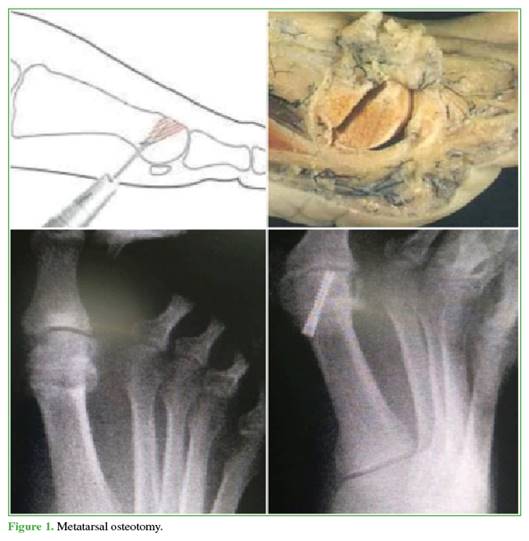

Distal osteotomy of the first metatarsal. Through the same percutaneous portal, a dorsal wedge osteotomy is performed using a long Shannon burr. Osteoclasis is then performed to close the osteotomy, followed by fixation with a compression screw, placed from proximal to distal and from medial to lateral through the head of the first metatarsal, without breaching the articular surface (Figure 1).